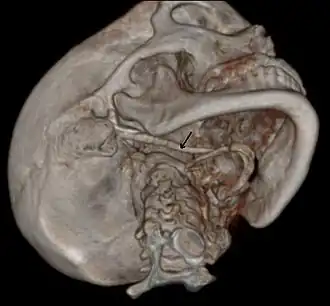

Imaging is important and is diagnostic. Visualizing the styloid process on a CT scan with 3D reconstruction is the suggested imaging technique.[13] The enlarged styloid may be visible on an orthopantogram or a lateral soft tissue X ray of the neck.